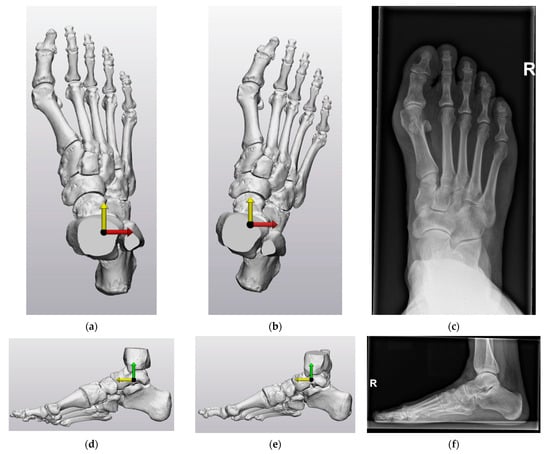

- Be clinically relevant with recognizable anatomical planes. This is necessary for the clinical interpretation of the deformity. When the virtual AP and lateral views of the coordinate system correspond with the corresponding radiographic images, a coordinate system is clinically relevant and has recognizable anatomical planes;